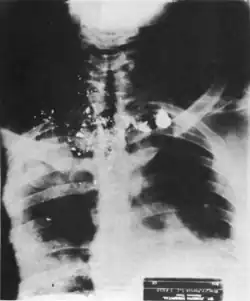

The X-ray of Dr. Martin Luther King after his death, but before his autopsy.

Shortly after King was pronounced dead, his body was moved from St. Joseph's Hospital to John Gaston Hospital, where Dr. Jerry Francisco conducted an autopsy at roughly 10:45 p.m., first published in Shelby County, Tennessee, on April 11, 1968.[1][40] At the time of his death, King was described measuring at 69.5 inches (5'9 ft, 176.5 cm) in height, about 140 pounds in weight, and was 39 years of age.[75]

The anatomical diagnosis by Dr. Francisco stated that:

Death was the result of a gunshot wound to the chin and neck with a total transection of the lower cervical and upper thoracic spinal cord and other structures in the neck. The direction of the wounding was from front to back, above downward and from right to left. The severing of the spinal cord [...] was a wound that was fatal very shortly after its occurrence.[76]

— Dr. Jerry T. Francisco, autopsy report of Martin Luther King Jr., page 1.

It was further determined that King was struck on the right side of his face, about 1.5 inches away from "below the angle of the mouth." The bullet entered through the right mandible, before it entered King's right pleural cavity, fractured his jawbone, and exited by the right side of the chin. The bullet then re-entered through the base of King's neck, continuing through the right supraclavicular fossa.[40][77] The bullet left a 3-inch wound in King's right cheek, and injured his external jugular vain, vertebral artery, and subclavian artery, before lodging itself near the back of the left scapula.[40][77]

3 bullet fragments found and removed from King after he was assassinated.

There was also an 8-inch scar above King's right breast, and a 6.5 inch scar on his upper chest. However, these scars were attributed to the 1958 assassination attempt, not the bullet fired by Ray.[40][78] After the bullet was removed from King's body, it was determined that there were no other pertinent findings. The official cause of death was listed as "hemodynamic collapse from hemorrhagic shock." Even if King had survived, it was determined that the injuries inflicted to King's spinal cord would have left him quadriplegic.[40] King also had a blood alcohol level of 0.01% found in samples of his blood and urine.[75][78]

3 bullet fragments were recovered from King's body, which were found in King's back during the process of the autopsy, and was extracted by Dr. Francisco.[75] Finally, according to Ben Branch, King's autopsy also revealed that his heart was in the condition of a 60-year-old man rather than that of a 39-year-old such as King, which Branch attributed to the stress of King's 13 years in the civil rights movement.[79]